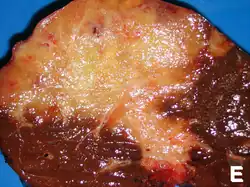

Although cholangiocarcinoma is known to have the histological and molecular features of an adenocarcinoma of epithelial cells lining the biliary tract, the actual cell of origin is unknown. Recent evidence has suggested that the initial transformed cell that generates the primary tumor may arise from a pluripotent hepatic stem cell.[41][42][43] Cholangiocarcinoma is thought to develop through a series of stages – from early hyperplasia and metaplasia, through dysplasia, to the development of frank carcinoma – in a process similar to that seen in the development of colon cancer.[44] Chronic inflammation and obstruction of the bile ducts, and the resulting impaired bile flow, are thought to play a role in this progression.[44][45][46]

Histologically, cholangiocarcinomas may vary from undifferentiated to well-differentiated. They are often surrounded by a brisk fibrotic or desmoplastic tissue response; in the presence of extensive fibrosis, it can be difficult to distinguish well-differentiated cholangiocarcinoma from normal reactive epithelium. There is no entirely specific immunohistochemical stain that can distinguish malignant from benign biliary ductal tissue, although staining for cytokeratins, carcinoembryonic antigen, and mucins may aid in diagnosis.[47] Most tumors (>90%) are adenocarcinomas.[48]

Pathology

Histologically, cholangiocarcinomas are classically well to moderately differentiated adenocarcinomas. Immunohistochemistry is useful in the diagnosis and may be used to help differentiate a cholangiocarcinoma from hepatocellular carcinoma and metastasis of other gastrointestinal tumors.[66] Cytological scrapings are often nondiagnostic,[67] as these tumors typically have a desmoplastic stroma and, therefore, do not release diagnostic tumor cells with scrapings.